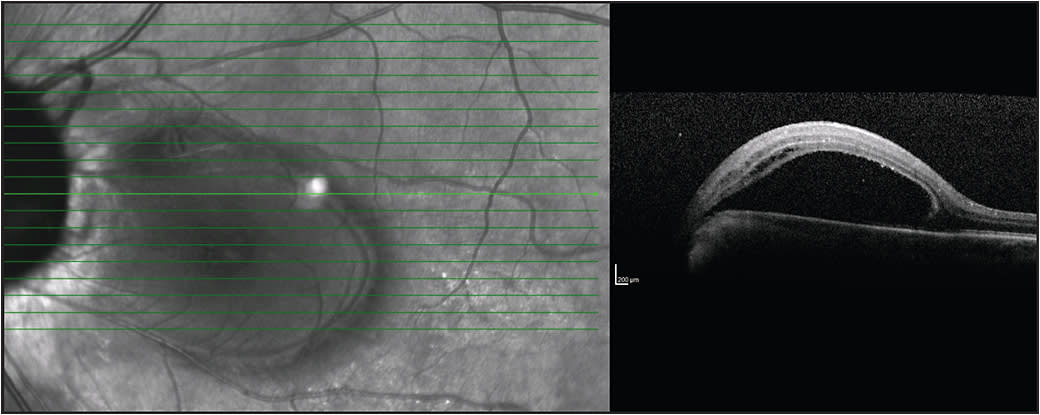

Figure 3. ODP maculopathy is a neurosensory detachment that can often be associated with a macular schisis. Top) Neurosensory detachment only. Bottom) Combined neurosensory detachment with a schisis.